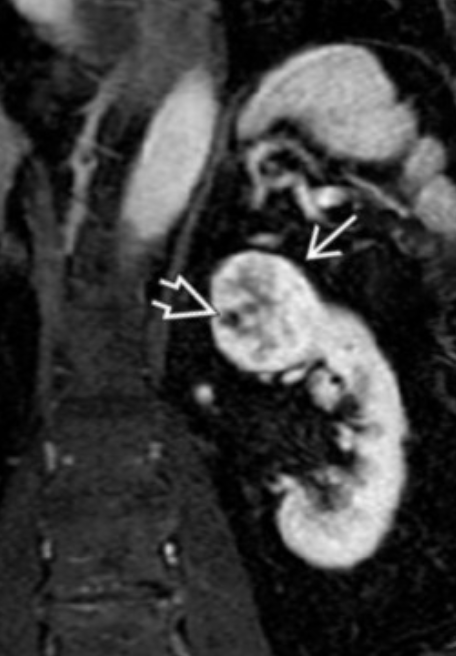

Medullary Sponge Kidney

• Dilatation of medullary and papillary ducts

• Commonly from tiny stones

• Presents as recurrent renal colic/flank pain

• In image below you see dilated ducts that the arrows point to and i guess normally you should not see them